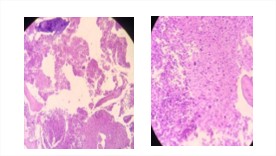

Causa intermedia muerte: Infiltración tumoral de linfoma no Hodgkin difuso de células grandes a hígado, bazo, páncreas, pulmón y médula ósea, (figura 3 y 4).

Infiltración tumoral de LNH en hígado

Figura 3: Corte histológico de hígado que muestra infiltración tumoral de linfoma no hodgkin (LNH). H/E, 10x y 40x.

Infiltración tumoral de LNH en médula ósea

Figura 4: Médula ósea hipercelular que muestra agregados nodulares de células atípicas, infiltración tumoral de LNH. H/E, 10 y 40x.